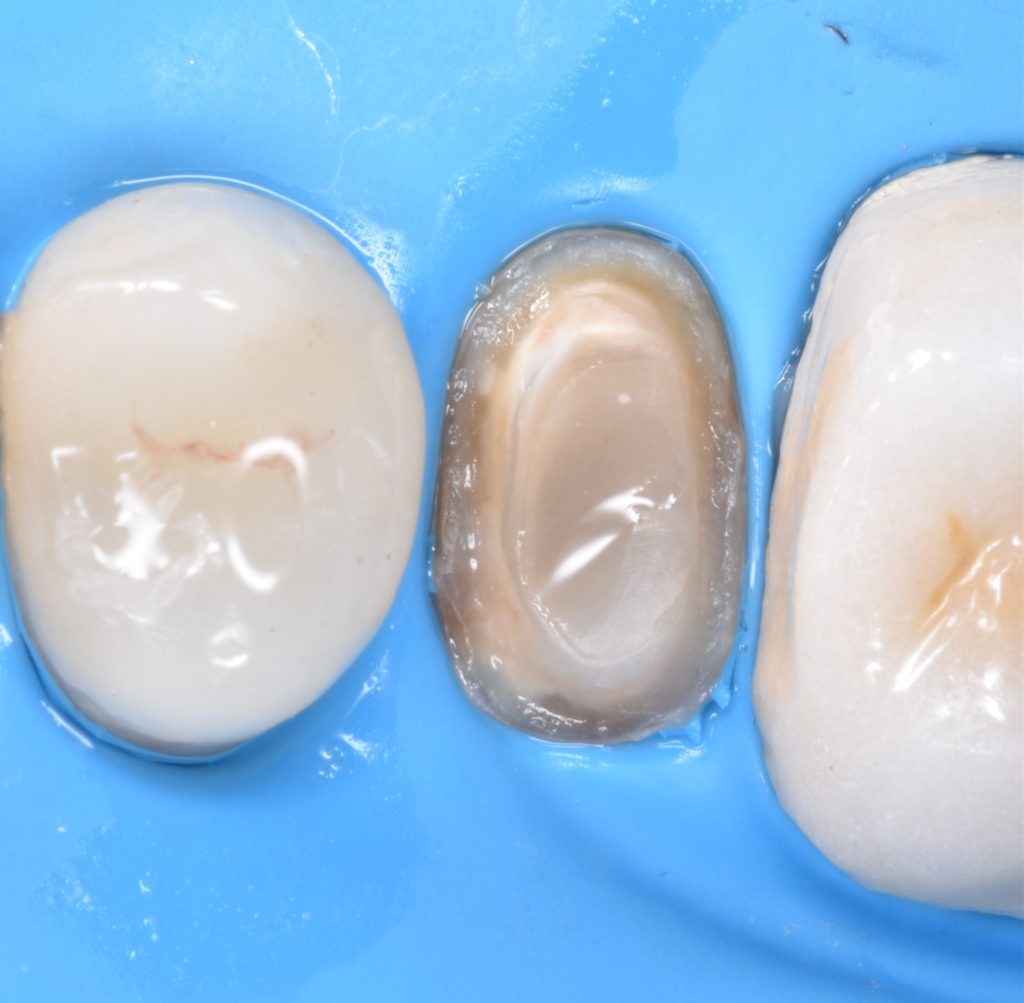

Caries removal with aid of caries detector dye

Deep margin elevation using circumferencial Copper bands

Elevation by snow plow technique n

And final design to receive to monolithic lithium disilicate restorations